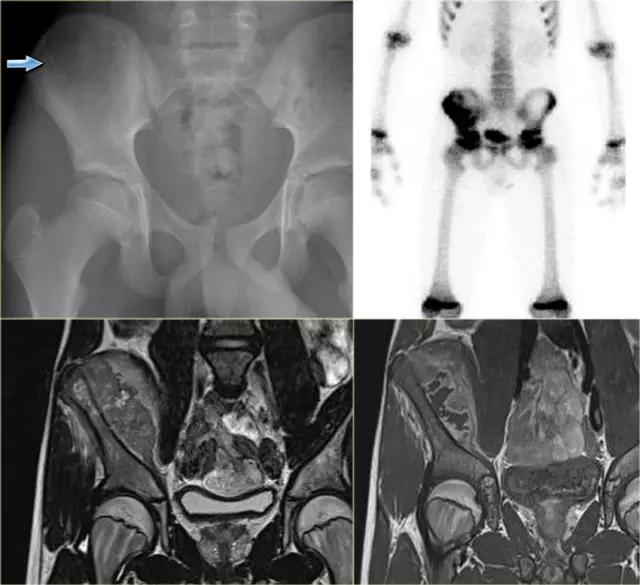

上图为一个年轻患者,右髂骨的一个不明确的溶解性病变,很容易被忽视。

最终诊断:尤因肉瘤。